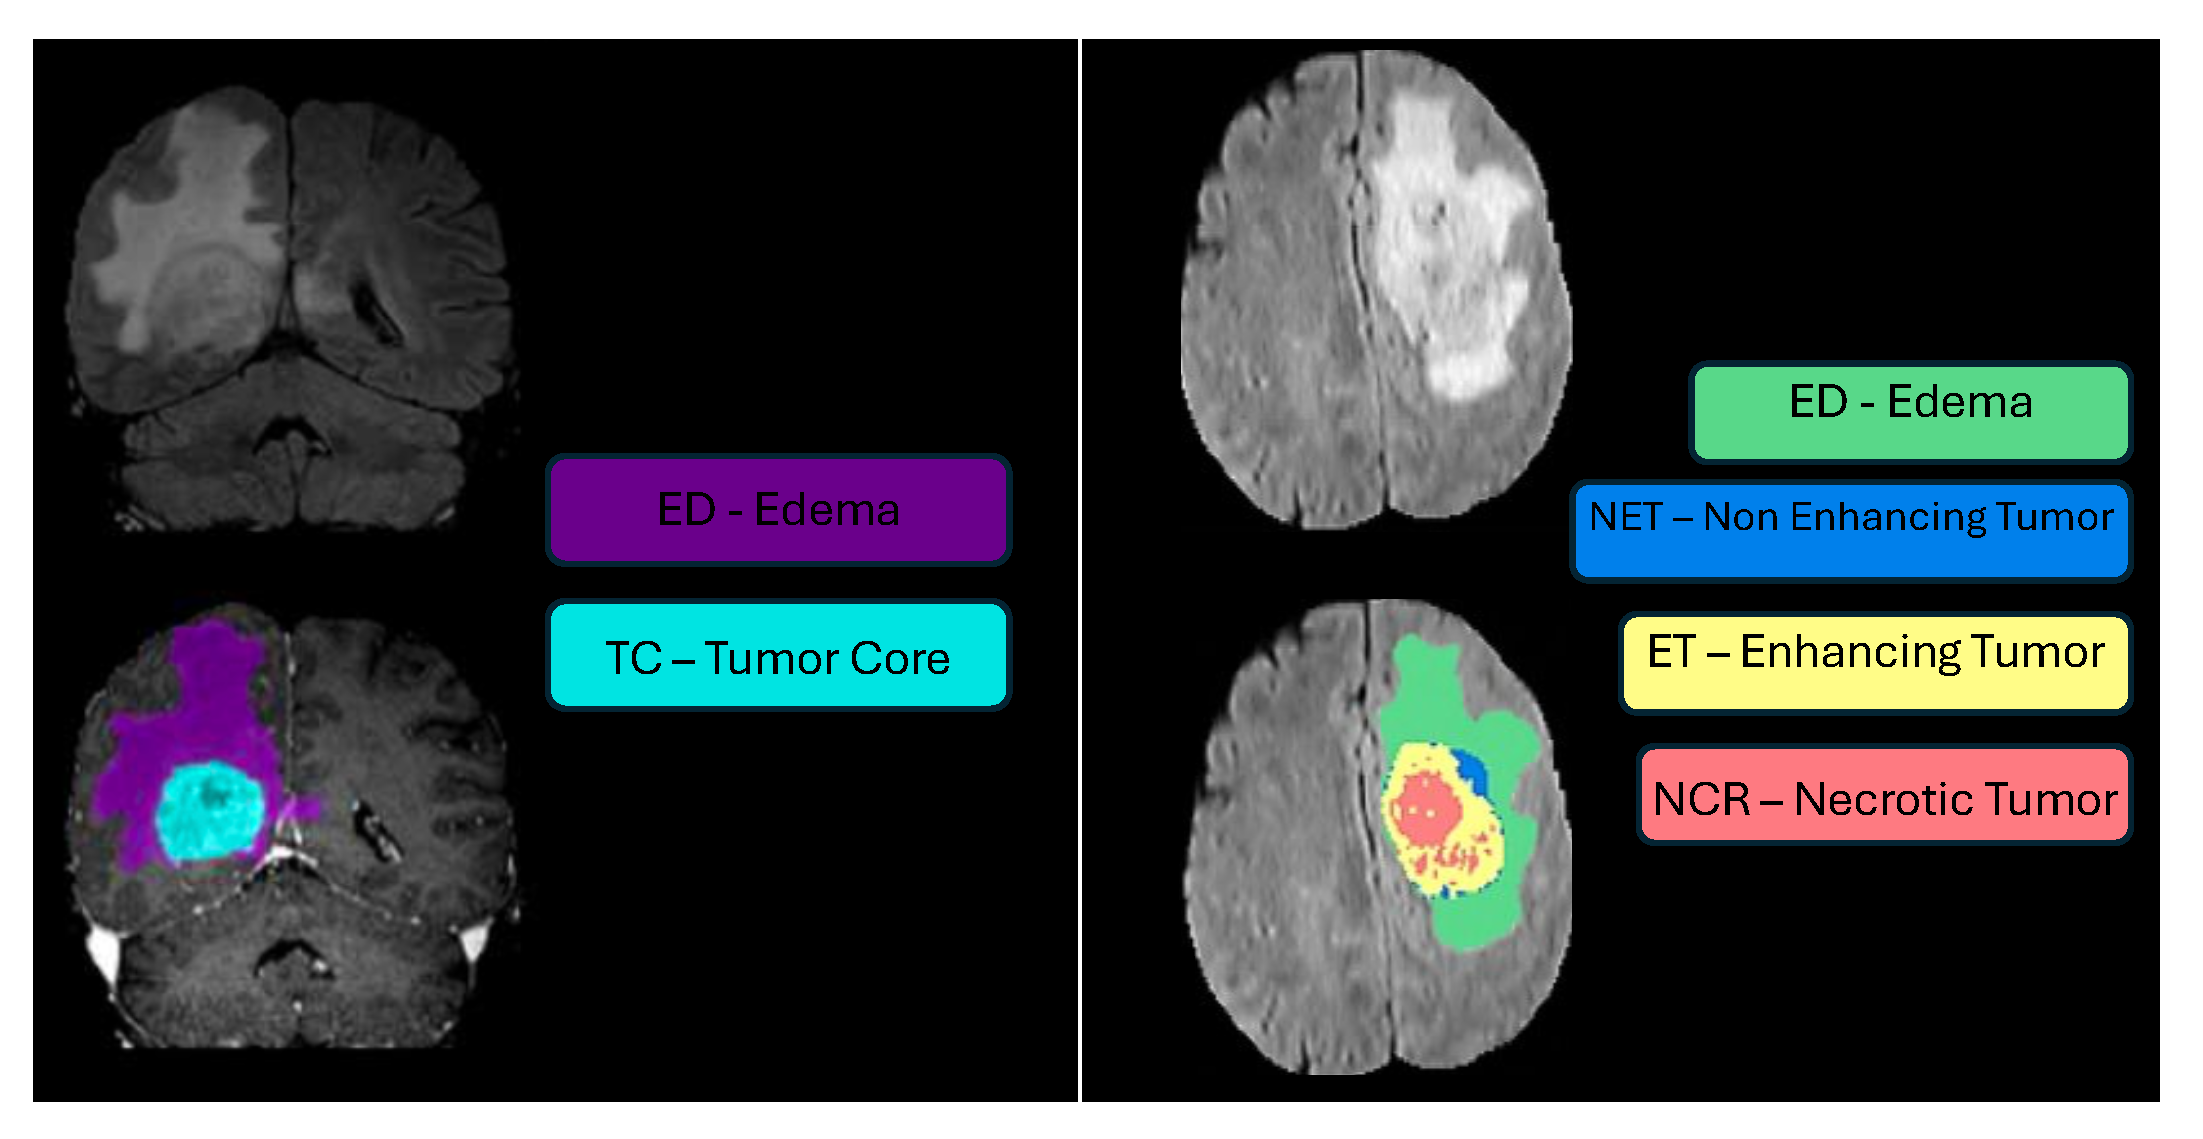

Segmentation - BraTS-Africa Dataset: All imaging data were reviewed and manually annotated by board-certified radiologists specializing in neuro-oncology, following the BraTS pre-processing and annotation protocols [10]. The new BraTS segmentation labeling introduced in 2023, and also used for the BraTS-Africa 2023 challenge, considers the following tumor sub-regions and can be visualised in Figure ii:

- Enhancing tumor (ET): Represents all tumor portions with a noticeable increase in T1 signal on post-contrast images compared to pre-contrast images, excluding adjacent blood vessels, intrinsic T1 hyperintensity, or abnormal signal in non-tumor tissues;

- Non-enhancing tumor core (NETC): Includes all non-enhancing tumor core areas, such as necrosis, cystic changes, calcification, and other non-enhancing components. Intrinsic T1 hyperintensity (e.g., intratumoral hemorrhage or fat) is also included;

- Surrounding non-enhancing FLAIR hyperintensity (SNFH): Covers the full extent of FLAIR signal abnormalities surrounding the tumor that are unrelated to the tumor core. For meningiomas, this corresponds to "vasogenic edema," excluding non-tumor-related FLAIR abnormalities like prior infarcts or microvascular ischemic changes.